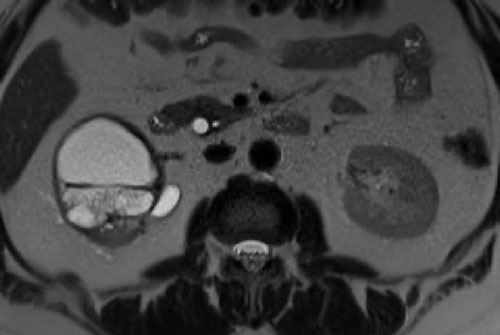

Có một khối dạng nang ở thận trái với nhiều vách ngăn mỏng ngấm thuốc.

Tổn thương được phân loại là Bosniak IIF.